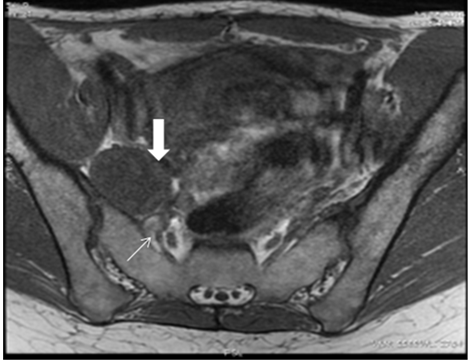

Computed tomography (CT) scan of the pelvis reported the presence of a 4.5 cm nodular lesion, located deep in the right pelvic region (Figure 1). Magnetic resonance imaging (MRI) scan showed a dependent right sciatic nerve lesion (Figure 2). The lesion contacted with the anterior surface of the sacrum and medially displaced the right hypogastric artery (Figure 3).

Figure 3: Magnetic resonance imaging T1-weighted axial image: A well-defined hypointense mass (arrow) adjacent to the hypogastric vessels (arrow) is noted.

Pelvic schwannomas are usually diagnosed incidentally, as solitary lesions, although some patients report abdominal pain or chronic sciatica. In case of chronic sciatica with no signs of radicular compression at MRI, the sciatic nerve must be radiologically examined all along its course [6]. Preoperative imaging tests are useful in determining the size, location and relationship of the lesion with neighboring tissues. Computed tomograhpy (CT) scan usually reveals a well-circumscribed lesion, with round or oval slight enhancement. Schwannomas are seen as isointense lesions on T1-weighted MRI and hyperintense on T2-weighted MRI scan. However, many schwannomas may show mix intensity on both T1- and T2-weighted images if they are associated with cystic degeneration, necrosis and (or) hemorrhage within the tumor [7]. Neurofibromas should be considered in the differential diagnosis. An eccentric association with the nerve is suggestive of a schwannoma.